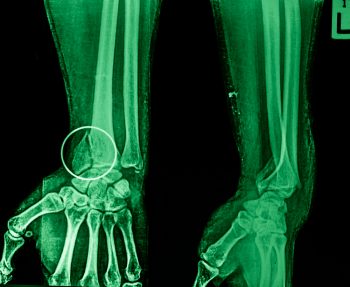

рентгенография Автор Екатерина Михайлюк | дата обновления 06.03.2017Мой мирВконтактеОдноклассники Рубрика: Поделись в соцсетяхВконтактеОдноклассники